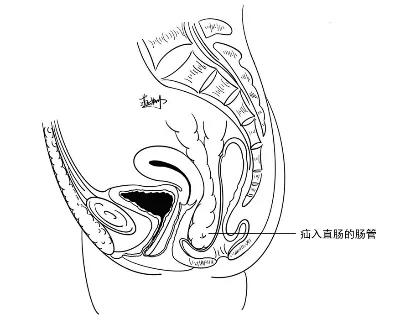

盆底腹膜疝的内容物大多为肠管,少数情况下可为大网膜或部分子宫。盆底腹膜疝可分为 3 类:直肠型、隔型及阴道隔型。

盆底腹膜疝-直肠型(作者自己画的)